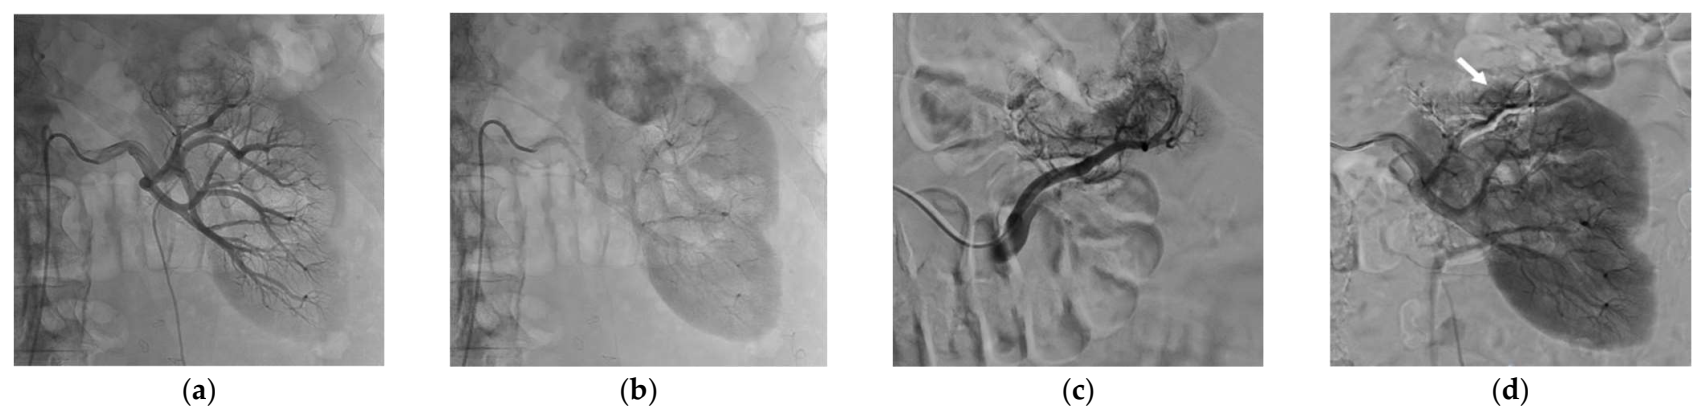

Successful SAE was achieved for all patients, but complete SAE in 11 patients (57.9%). Complete SAE could not be achieved in the remaining eight patients since it would have led to an unacceptable loss of surrounding healthy tissue. However, for cases with incomplete embolization, devascularization was obtained for most of the tumor volume, always greater than 50% on control angiogram. The most used NBCA/Lipiodol® ratio range was 1/3 to 1/5, in 18 patients. Mean procedure time was 93 ± 43 min and mean fluoroscopy time was 18 ± 11 min. The mean DSP for the SAE procedure was 120.7 ± 68.7 Gy.cm2. The mean volume of injected contrast medium was 119 ± 50 mL. The mean NRS pain score was 0.89 ± 1.52 after SAE. Table 3 lists the main characteristics of the SAE procedure. Figure 1 and Figure 2 show examples of SAE of renal cell carcinoma before PCA.

Figure 1.

Selective arterial embolization (SAE) procedure using NBCA/Lipiodol® mixture performed before percutaneous cryoablation of a renal cell carcinoma of the left kidney. (a) Angiogram showed hypervascularization of the renal malignancy with one feeding artery. (b) Control angiogram after SAE using NBCA/Lipiodol® mixture (1/5 ratio) showing the complete occlusion of the tumor vessels and devascularization of the tumor whereas the surrounding healthy tissue was spared.

Figure 2.

Selective arterial embolization (SAE) procedure using NBCA/Lipiodol® mixture performed before percutaneous cryoablation of a renal cell carcinoma of the upper pole of the left kidney. (a,b) Angiogram showed hypervascularrenal malignancy. (c) Selective angiogram after embolization of a feeding artery of the tumor showing another feeding artery with residual tumor blush. (d) Control angiogram showing the occlusion of the two major feeding arteries after embolization with a small residual tumor blush (white arrow).